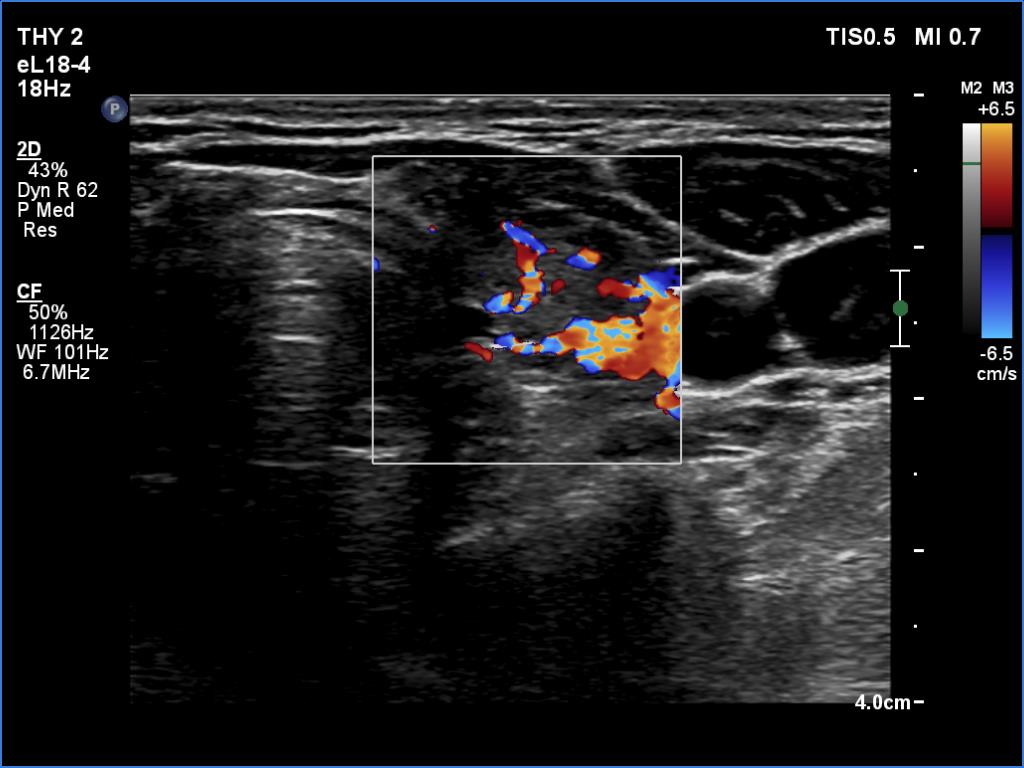

Parathyroid lesions - case 1521 (ultrasonographic picture 9)

Left lobe, transverse scan, color Doppler mode. The vascularity is increased.